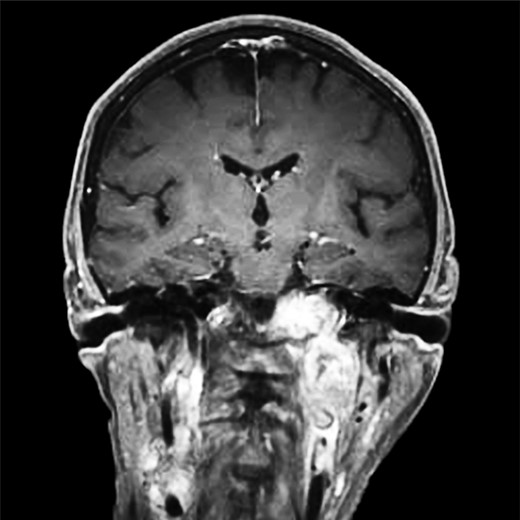

(A and B) Magnetic resonance images, coronal planes, highlight three of the four previously noted cervical PGLs decreasing in size, with the right inferior PGL remaining unchanged.

(A and B) Magnetic resonance images, sagittal and coronal planes, show increased left-sided carotid PGL, with significant extension into the jugular foramen and skull base.